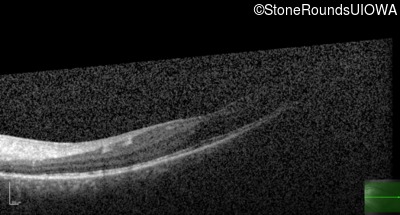

This 16 year old male had an untreatable retinal detachment discovered in his right eye at age 3. A year later he developed a retinal detachment in his left eye which was successfully repaired with a combination vitrectomy and scleral buckle. The visual acuity gradually improved to 20/30 following surgery.

Age at visit: 15 years